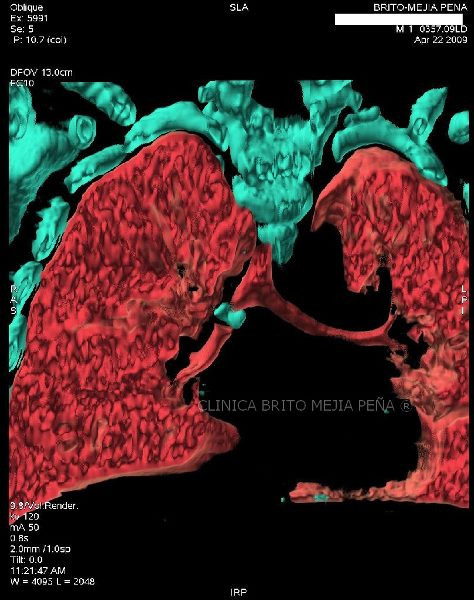

Cuerpo extraño en bronquio derecho 3D